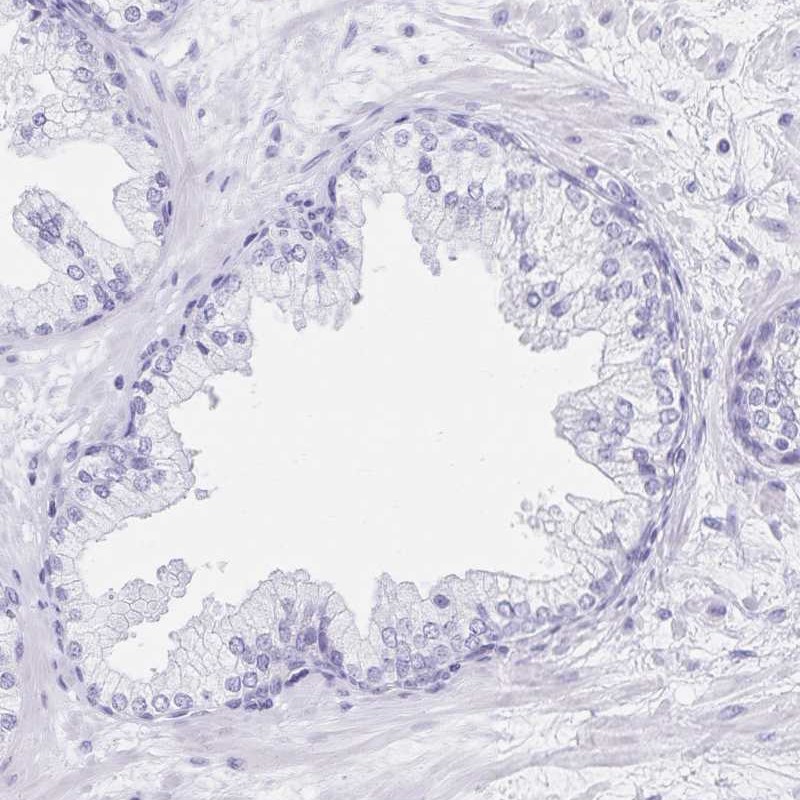

Immunohistochemistry analysis in human fallopian tube and prostate tissues using Anti-C2orf50 antibody. Corresponding C2orf50 RNA-seq data are presented for the same tissues.